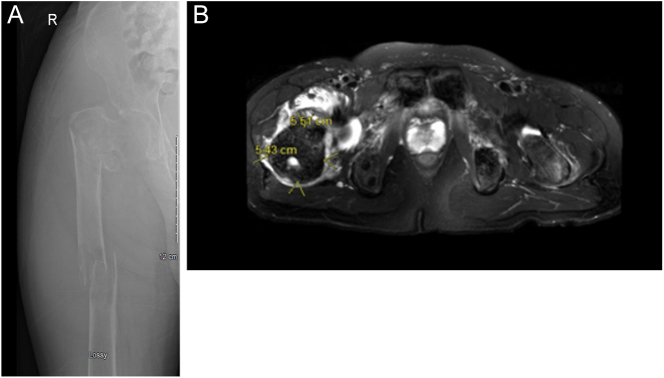

Summary: Primary hyperparathyroidism (PHPT) is a disorder in which excessive parathyroid hormone (PTH) is secreted from the parathyroid glands. The cause of PHPT is most commonly parathyroid lesions such as parathyroid adenoma. The clinical manifestations of PHPT include hypercalcemia, nephrolithiasis, bone disease and rarely pathological fractures and brown tumors, which arise within the foci of osteitis fibrosa. Brown tumors are benign intraosseous tumors that occur because of excessive osteoclast activity. Because of advances in medical care, early diagnosis and treatment have meant that diagnosing PHPT in the setting of multiple brown tumors is particularly rare. Here, we present a case of a young man with prolonged PHPT from a giant parathyroid adenoma with multiple brown tumors causing pathological fractures. Definitive treatment of PHPT is parathyroidectomy with particular attention to the risks for hungry bone syndrome (HBS) postoperatively.

Learning points: Pathological fractures from brown tumors are a rare but significant concern in prolonged PHPT, and a multidisciplinary approach is required including orthopedic surgery, otolaryngology and endocrinology.It is important to assess PTH and calcium in the context of hypercalcemia with bone lesions to avoid potential diagnostic delays.Postoperative parathyroidectomy patients with large parathyroid adenomas, elevated alkaline phosphatase, elevated PTH and the presence of brown tumors are at particularly high risk for HBS.Very high levels of PTH, calcium, alkaline phosphatase and multiple brown tumors should raise concern for a potential case of parathyroid carcinoma.Indications for genetic testing for inheritable parathyroid disease include patients younger than 30 years old, those with multigland disease, those with a family history of hypercalcemia or syndromic disease and those with atypical parathyroid adenoma and parathyroid carcinoma.